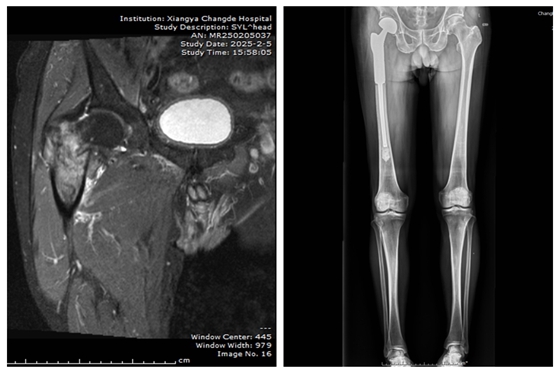

患者术前影像资料 患者术后影像资料

一位68岁的李叔叔,两个月前开始出现右髋关节疼痛并伴有活动受限的情况,辗转多家医院治疗未见明显好转。 来到我院后,经过一系列检查,确诊他是因为前列腺癌导致的骨转移,引发了股骨颈病理性骨折。进一步评估发现,李叔叔不仅有前列腺原发肿瘤,而且股骨颈和股骨粗隆间都有癌灶转移,同时还伴有低蛋白血症、低钙血症和肺部感染等复杂病情。

为了给李叔叔提供最佳的治疗方案,医院组织了泌尿外科、肿瘤科、放射科、麻醉科、重症监护室等多学科会诊。考虑到患者的单发转移灶和严重的右下肢疼痛及活动障碍,内科治疗效果不佳且副作用大,最终决定采取外科手术作为最佳治疗方案。由何洪波教授主刀,联合周天宝主任医师、林开胜副主任医师、苏宏伟主治医师组成的医疗团队为患者进行了股骨近端肿瘤切除+人工髋关节假体置换术。由于患者骨折类型特殊且肿瘤切除范围较广,常规治疗方法无法满足需求,术中使用了特殊的肿瘤型髋关节假体。手术顺利完成,患者康复出院。

此次手术不仅成功切除了李叔叔的骨肿瘤病灶,还通过肿瘤型髋关节假体的置换极大地改善了他的生活质量。术后,李叔叔的右髋关节疼痛明显减轻,活动能力得到恢复,术后45天已经可以在辅助下行走。这项技术的成功开展,不仅为晚期肿瘤骨转移患者提供了新的治疗选择,也展示了湘雅常德医院在复杂骨肿瘤手术治疗方面的综合实力。